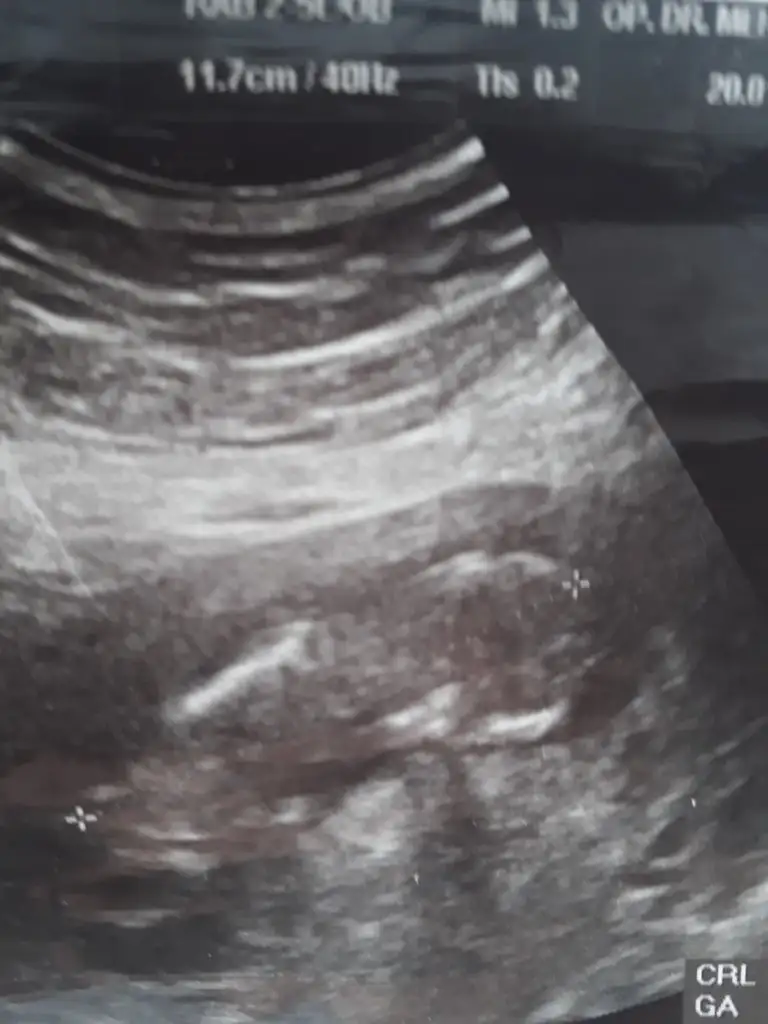

11 yada 129 haftalığız Acaba bizede tahmin yapabilirmisiniz yoksa 11 12yimi beklemeliyim![]()

Kaç haftalık sanki kız gibi 12 hafta paylaşınBanada bi tahminiz var mı![]()

13 haftalık :) doktor söylemedi cinsiyetini yanıltıcı olabilir dedi. Tahmini ni bile söylemediKaç haftalık sanki kız gibi 12 hafta paylaşın